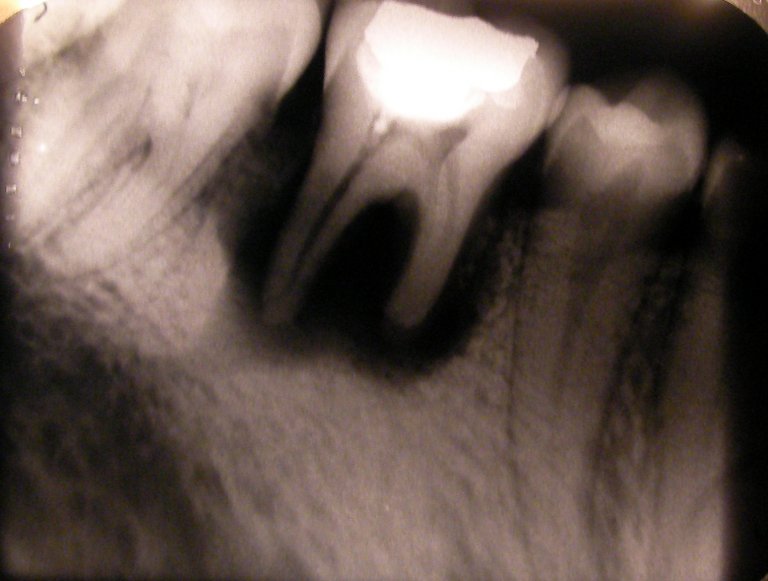

Tooth resorption. A/B) Clinical photograph and radiograph of maxillary... Download Scientific

From www.researchgate.net

Tooth resorption. A/B) Clinical photograph and radiograph of maxillary... Download Scientific Is Tooth Resorption Dangerous Bone cells or the presence of other teeth destroy. tooth resorption can lead to infections, crooked teeth, tooth loss, and other dental problems that can cause lasting damage to your. when root resorption happens outside of losing baby teeth, it’s likely due to tooth nerve or gum infection, tooth. tooth resorption is when the tooth structure is. Is Tooth Resorption Dangerous.